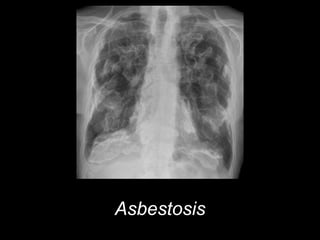

Asbestosis

• #47 Asbestosis

• #48 Asbestosis